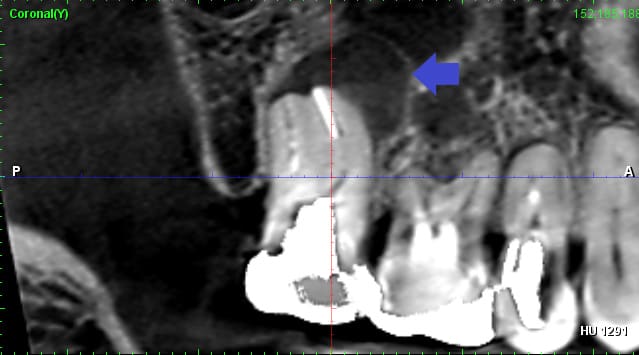

下顎右側の奥歯の歯茎が赤く腫れて歯肉に膿瘍がみられます(photo.6)。レントゲン画像とCT画像を確認すると歯根を取り巻くように歯槽骨の吸収がみられました(photo.7)。以上の所見より根尖性歯周炎が疑われました。また、膿が大きく、歯根破折も考えられるケースです。

下が治療6ヶ月後のCT画像です(photo.8)。膿の影が消失し歯根の周りの歯槽骨が再生しています。